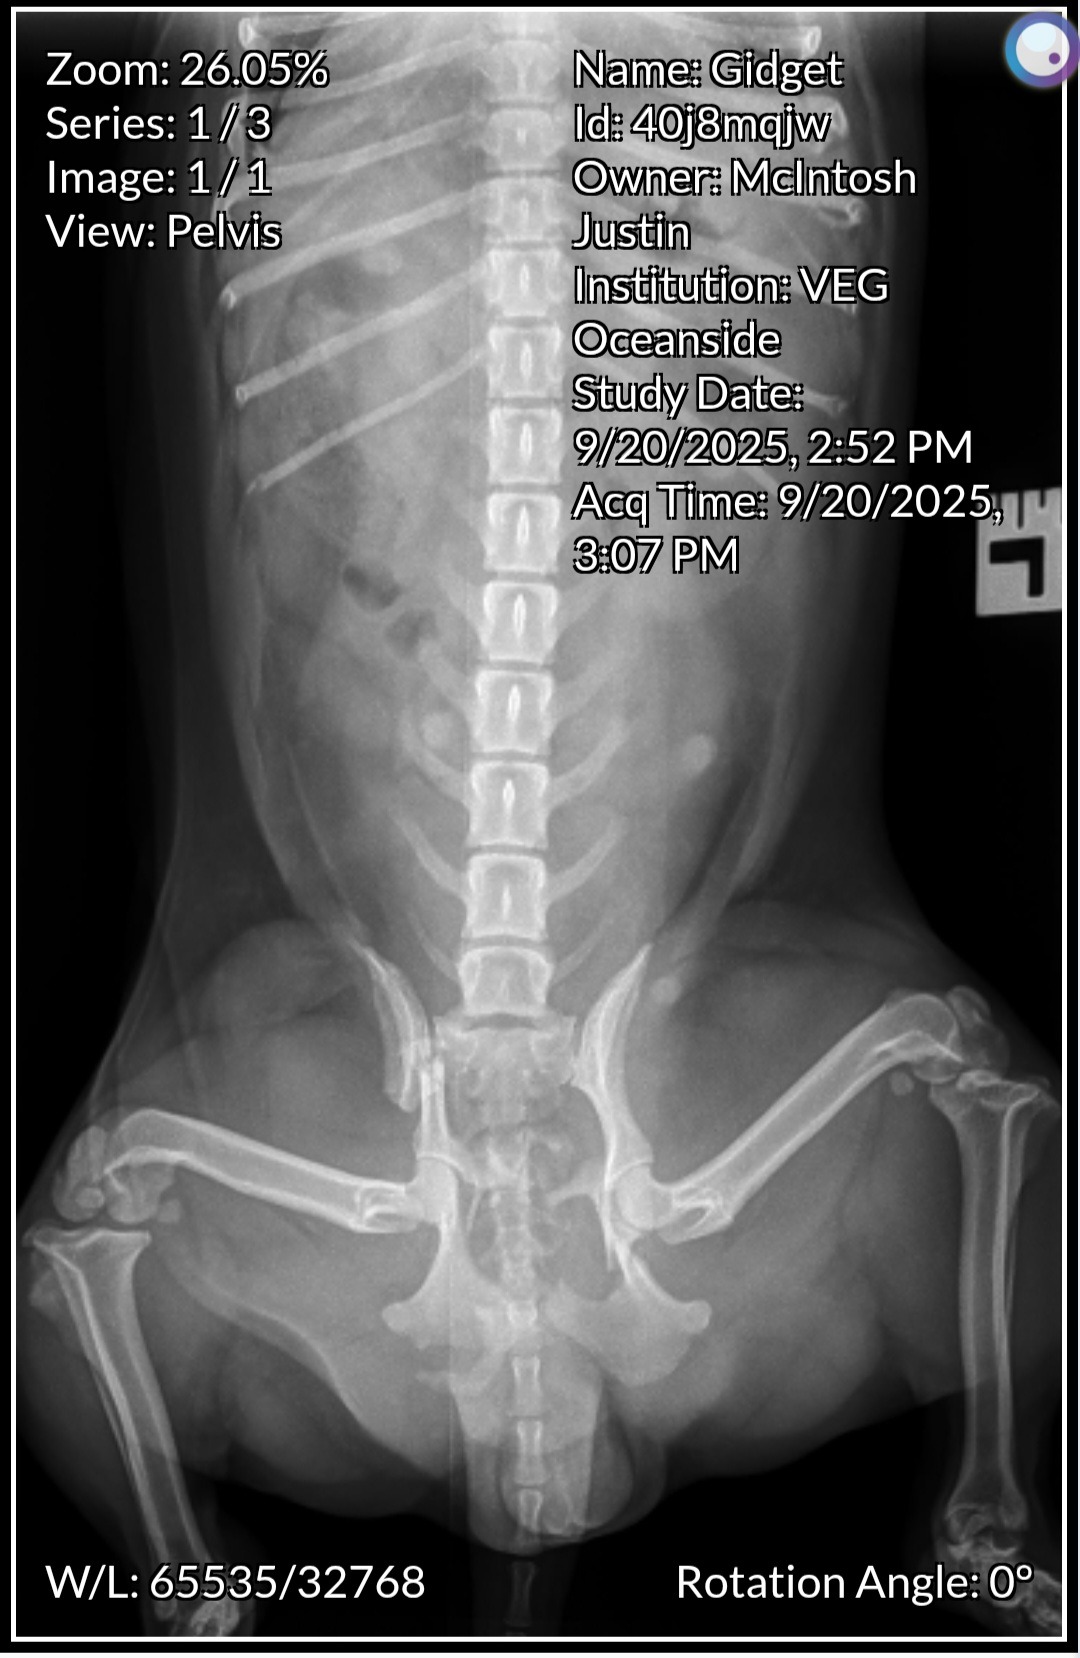

Hi, my name is Justin, and I’m fundraising for my sweet dog, Gidget. She’s only 1 year and 8 months old, full of life and love, but recently she was hit by a car and suffered multiple pelvic fractures—her pelvis is broken in four different places. She’s an incredibly strong girl, but she can’t heal properly without surgery.

The surgery is estimated at $5,700. I had managed to save $2,900 from working again after a very difficult time in my life. Of that, I’ve already spent $2,000 at the emergency vet for blood work and X-rays to get her stable and ready for surgery. That leaves me with $900, which is everything I have left right now—but it’s not enough to cover the operation she desperately needs.